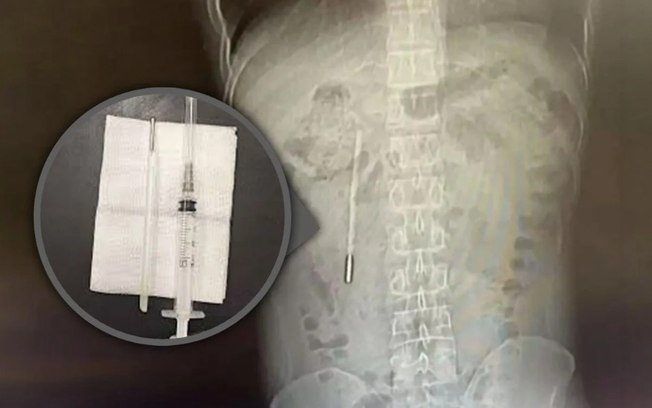

Termômetro encontrado em intestino de homem

Exames de imagem revelaram a presença de um objeto estranho no duodeno, parte inicial do intestino delgado. Os médicos suspeitaram imediatamente que se tratava de um termômetro de mercúrio, hipótese confirmada posteriormente.

De acordo com a equipe médica, a ponta do objeto pressionava diretamente a parede intestinal, o que representava alto risco de perfuração e hemorragia interna grave.

A remoção foi feita por cirurgiões em um procedimento que durou cerca de 20 minutos. Apesar da rapidez, a operação exigiu grande precisão, já que o objeto estava no organismo há muitos anos e próximo aos ductos biliares, aumentando o risco de lesões internas.

O termômetro foi retirado intacto, embora as marcações de medição já estivessem apagadas com o tempo.